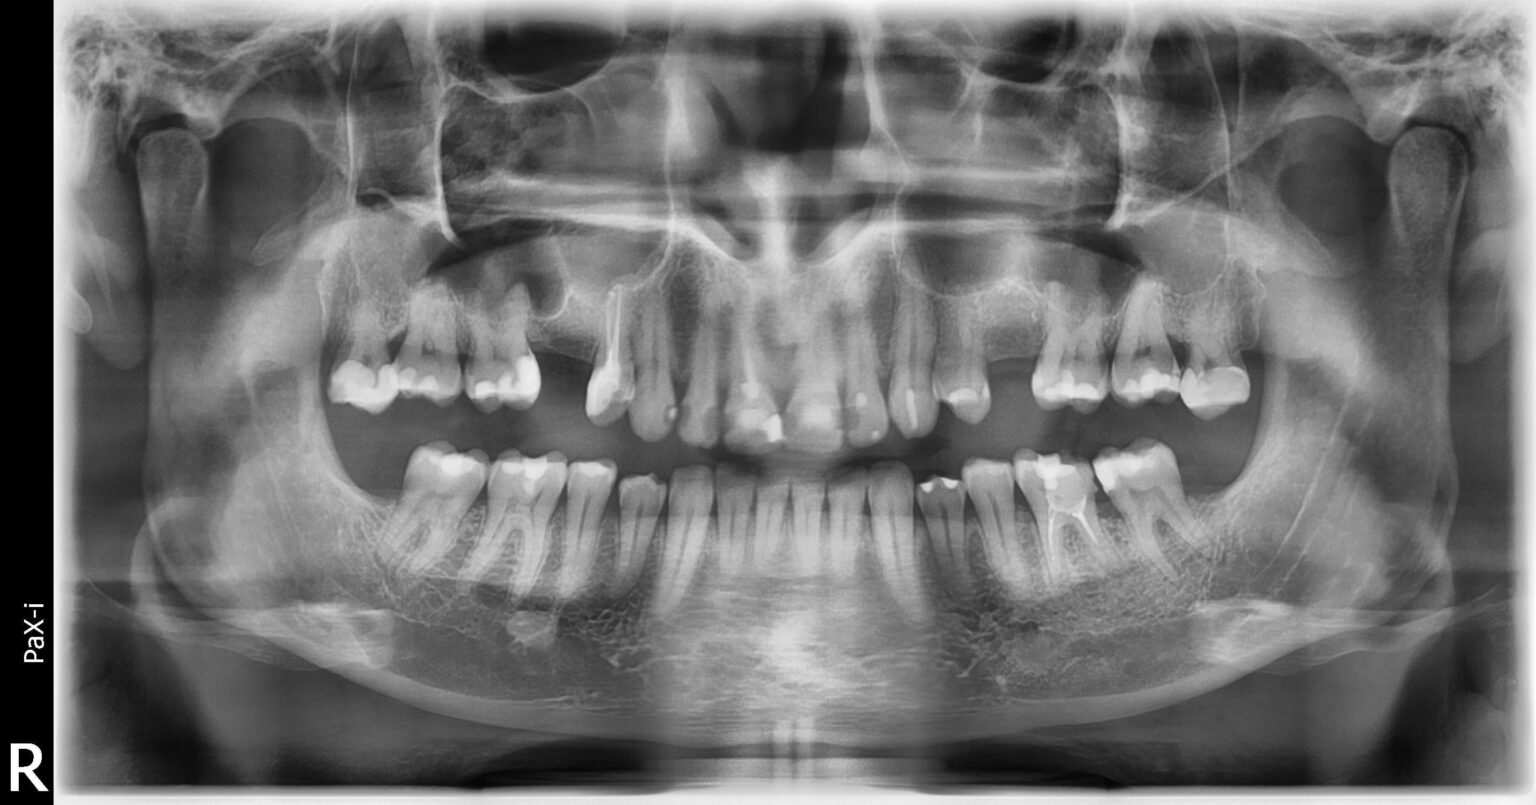

https://i.redd.it/006cvho010cg1.jpeg